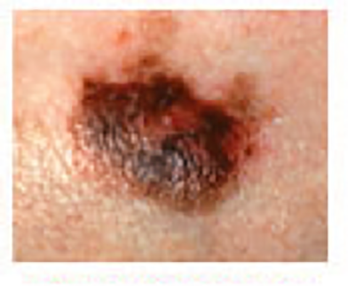

Melanoma Photos

Nodular melanoma on the leg of a Native American woman.

Photo: International Skin Imaging Collaboration

Amelanotic melanomas may be pinkish-looking, reddish, purple, normal skin color or essentially clear and colorless.

The power of denial can be strong. This man believed the large, dark growth on his back was a boil, despite oozing and bleeding for months. He kept bandaging it and thought it was just slow to heal. When he was finally referred to Dr. Sarnoff, a biopsy and other tests revealed a melanoma so large and deep that it had already spread to the man’s liver and brain. He was referred to an oncologist and began an immunotherapy regimen that did not appear to be working, which happens with some patients. (Thanks to recent innovations, there may be other treatment options, including participation in a clinical trial.) This is a powerful reminder of the importance of early detection.